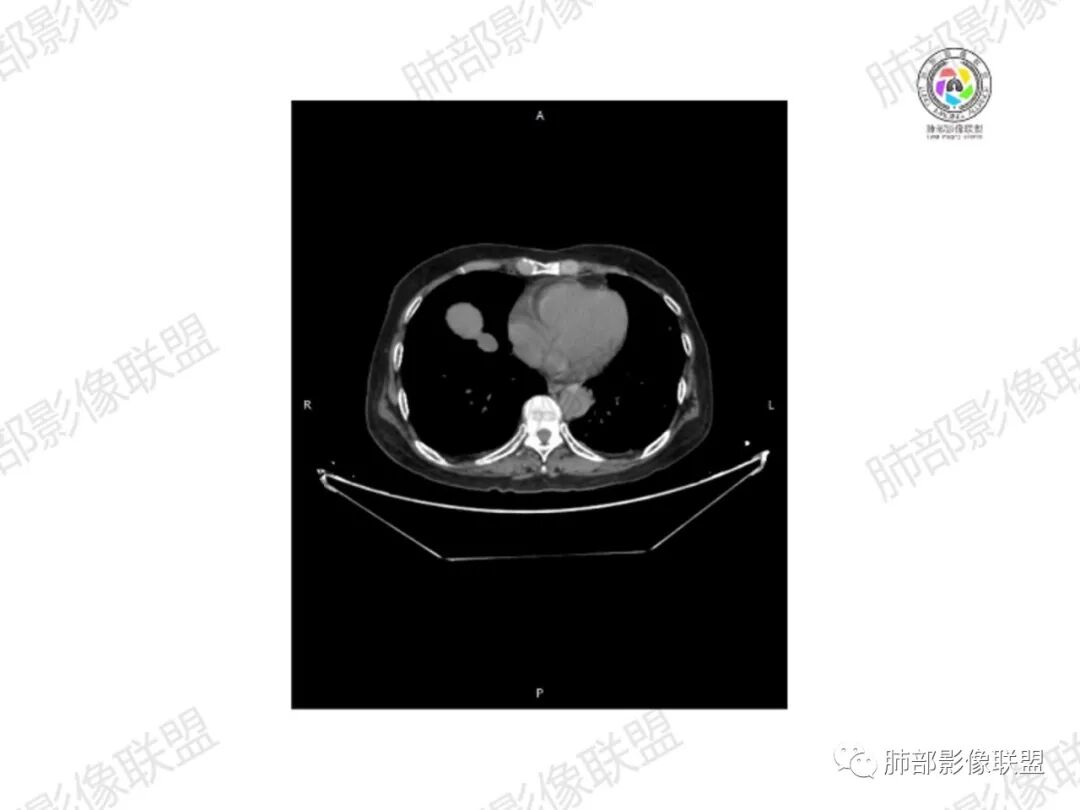

2.右髂骨轻度变形伴广泛骨质吸收破坏,边界不清且突破骨皮质。近中线区以溶骨性破坏为主,髂骨翼一侧则成骨性改变明显,骨表面见垂直骨针或花边样高密度瘤骨。

3.患骨多处皮质断裂,符合病理性骨折。注意折端可能会形成骨痂,但本例无论是形态还是部位都不符合骨痂。

4.患骨两旁(即盆骨内外)见边界不清的较大范围软组织快影,其间偶见骨化影。

5.双肺多发类圆形结节影,边界清楚,随机分布,其间多见钙化密度影。

6.双肺门及纵隔未见肿大淋巴结。

1.边界不清的骨质吸收破坏,溶骨明显,骨皮质突破,软组织肿块,种种迹象表明其恶性无疑!

2.但注意这是有“成骨”的恶性骨肿瘤!我们知道老年患者的骨原发性恶性肿瘤“成骨”非常少见。少数转移瘤可为成骨型或混合型,女性患者如乳腺癌骨转移等。在男性,最典型的成骨转移是前列腺癌。

本例右侧髂骨具有较为典型的“骨肉瘤”影像学特征,有边界不清的吸收破坏、有新生骨、形成软组织肿块等等。

3.双肺病灶符合转移瘤,伴有中央部分钙化者也以骨肉瘤转移较为多见。